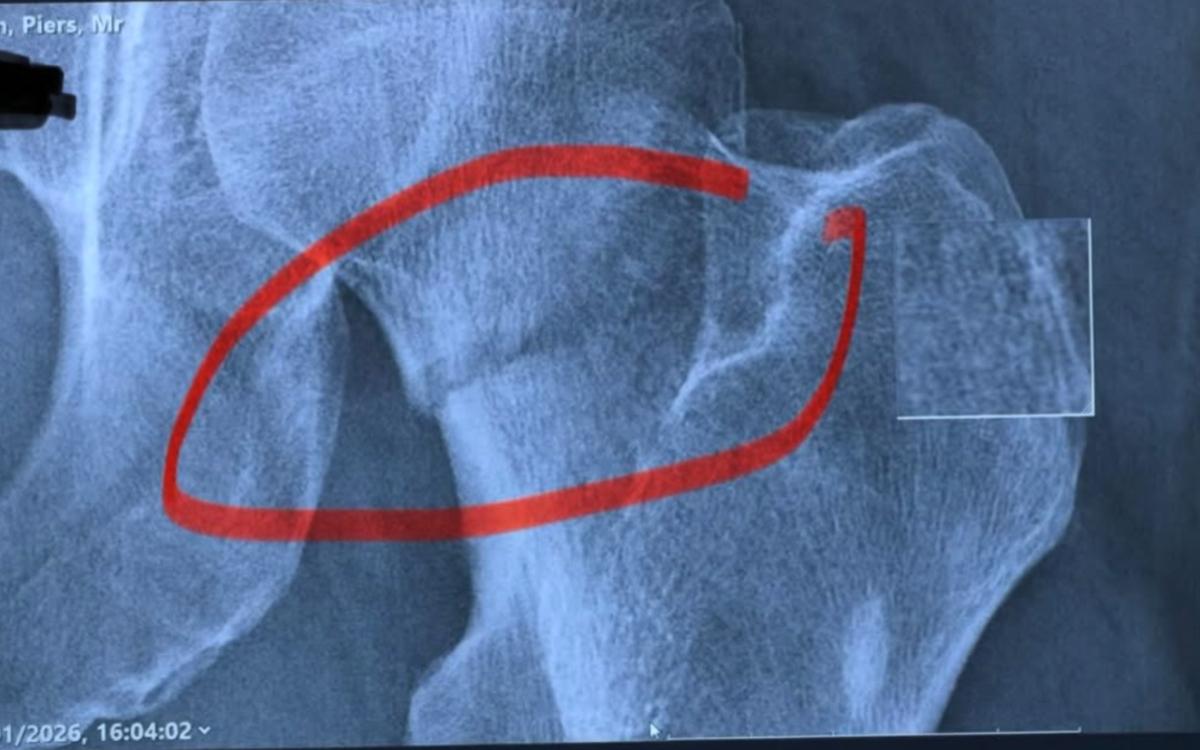

If you thought the pun train was done, we have great news for you; it's not. "Breaking News," wrote Morgan in the caption of his post beneath the hospital picture and a gnarly X-ray image of a fracture in his femur. The media personality tripped on a small step inside a London restaurant. This resulted in Morgan falling "like a sack of spuds."

This unfortunate tussle with gravity will required a new hip, crutches for six weeks, and no long-haul flying for 12 weeks. According to University Hospitals Plymouth, the fractured neck of one's femur is essentially a broken hip. This can be a serious injury, especially in individuals over the age of 65. Morgan is 60. "It occurs when the top part of the femur (leg bone) is broken, just below the ball and socket joint."